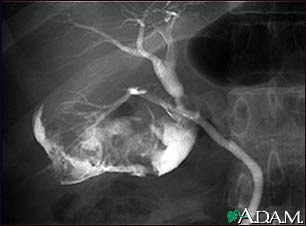

Cholecystitis, cholangiogram

Cholelithiasis can be seen on a cholangiogram. Radio-opaque dye is used to enhance the x-ray. Multiple stones are present in the gallbladder (PTCA).